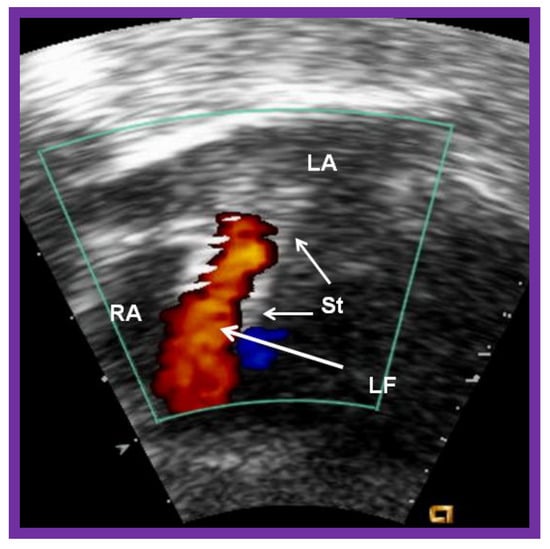

Figure 19.

Selected cine (A) and video (B) frames demonstrating the location of the stent (St) across the atrial septum following St deployment. LA, left atrium; RA, right atrium; PG, pigtail catheter in the descending aorta. Reproduced from Reference [89].

Figure 20.

Video frame of the stent (St) (short arrows) demonstrates laminar flow (LF) (long arrow) across it. LA, left atrium; RA, right atrium. Reproduced from Reference [89].